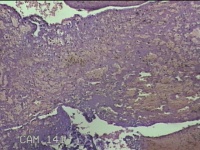

左侧卵巢黄体

性别

女

年龄

34岁

临床诊断

左侧卵巢黄体破裂

一般病史

下腹疼痛11小时。

标本名称

大体所见

灰白暗红色囊壁样组织3x2.3x0.3cm一堆,表面光滑,内壁高低不平,切面灰白暗红色,囊壁厚约0.1cm。

有可能,所提供图片不具有诊断价值。